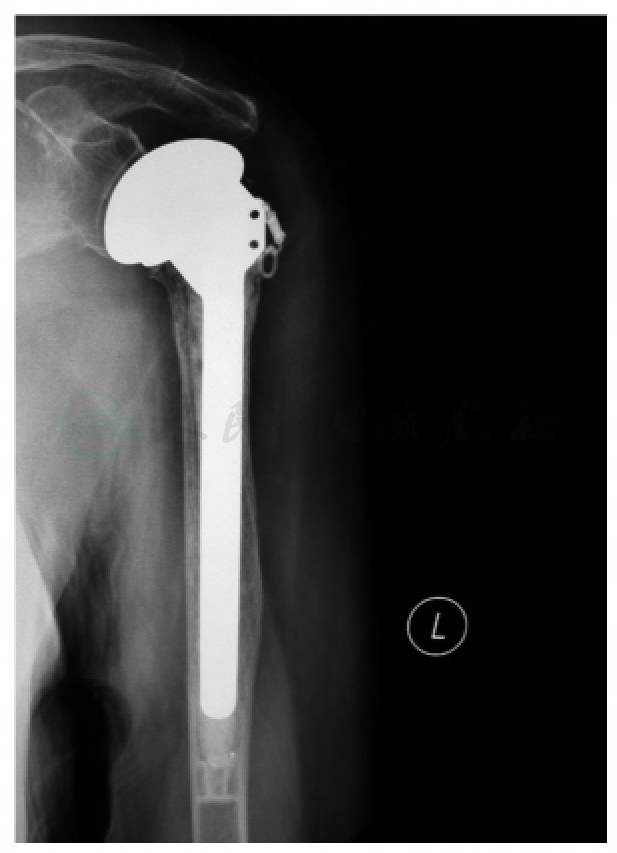

术后肩关节吊带固定,第1日开始患侧肘关节、前臂、腕和手的主动活动,术后第3日移除引流管。行X线检查示:假体位置良好(图4),即可开始肩关节被动活动。

图4 术后第3天X线片